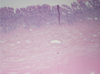

What type of epithelium is the stomach made of

Simple columnar

Where are there no blood vessels

mucosa. Once you see a vessel you know you are in the submucosa or lower

Stomach

Stomach

Stomach